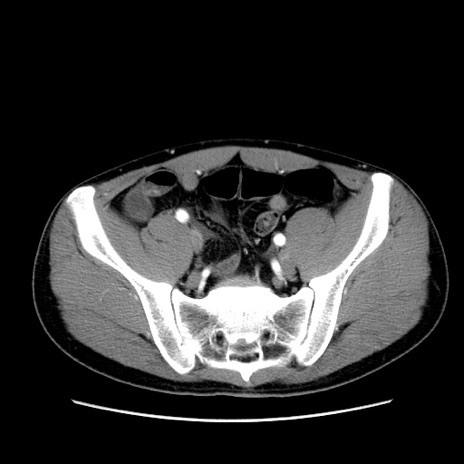

症例36(横断像)

【症例】20歳代 男性

【主訴】心窩部痛

【現病歴】今朝より上腹部痛あり。一旦軽快していたが再度出現したため救急要請。昨日夕に白身の魚を含む刺身を食べた。

【身体所見】BP 136/89mmHg、HR 74/min、BT 37.0℃、腹部:膨満、軟、心窩部に圧痛あり。反跳痛なし、筋性防御なし、腸雑音やや亢進あり。

【データ】WBC 17700、CRP 0.48